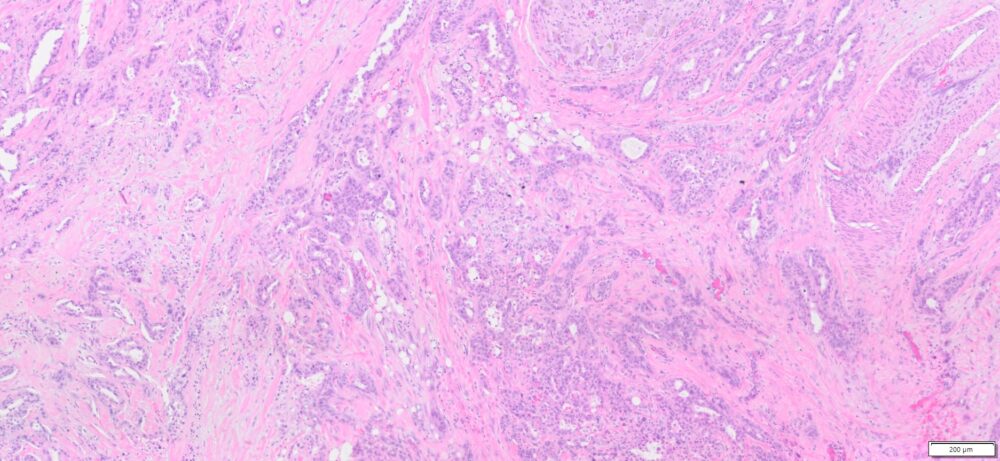

Description

| Tissue | Pathology Diagnosis | Gender/ Age (year) | %Tumor Area | Tumor Grade | TMN/Stage | IHC data |

| Pelvic mass | Human bile duct adenocarcinoma | Female/66 | 30% | II | T3N1M0 | MLH1,2,and6, PMS2 show intact nuclear expression |